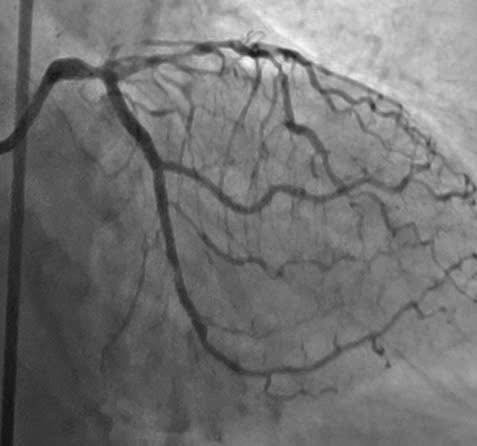

TS. Shozo Ishihana – Bệnh viện Đa khoa Mimihara, Osaka, Nhật Bản cùng các bác sĩ khoa Tim mạch thực hiện kỹ thuật can thiệp cho bệnh nhân T.- Ảnh BVCC

Để giải quyết tổn thương CTO của động mạch mũ vốn là thách thức lớn nhất cho tất cả các bác sĩ can thiệp vì những tổn thương này việc can thiệp rất khó khăn do mạch máu đã tắc và vôi hoá từ lâu, ê-kíp đã quyết định thực hiện ca can thiệp với sự hỗ trợ kỹ thuật từ TS. Shozo Ishihana – chuyên gia tim mạch can thiệp đến từ Bệnh viện Đa khoa Mimihara, Osaka, Nhật Bản.

Dưới sự dẫn đường của hệ thống chụp mạch xóa nền kỹ thuật số (DSA), đội ngũ bác sĩ đã phối hợp chặt chẽ, sử dụng các dụng cụ chuyên biệt gồm dây dẫn siêu nhỏ và siêu cứng (guidewire) với sự hỗ trợ của các vi ống thông (microcatheter) để tiếp cận và đưa dây dẫn qua vị trí tắc mạn tính của động mạch vành mũ. Sau đó, các bác sĩ đã đặt 01 Stent tái thông động mạch mũ một cách an toàn.

Toàn bộ ca can thiệp diễn ra trong 45 phút căng thẳng, đòi hỏi kỹ năng chuyên sâu, sự phối hợp nhịp nhàng và tập trung cao độ.